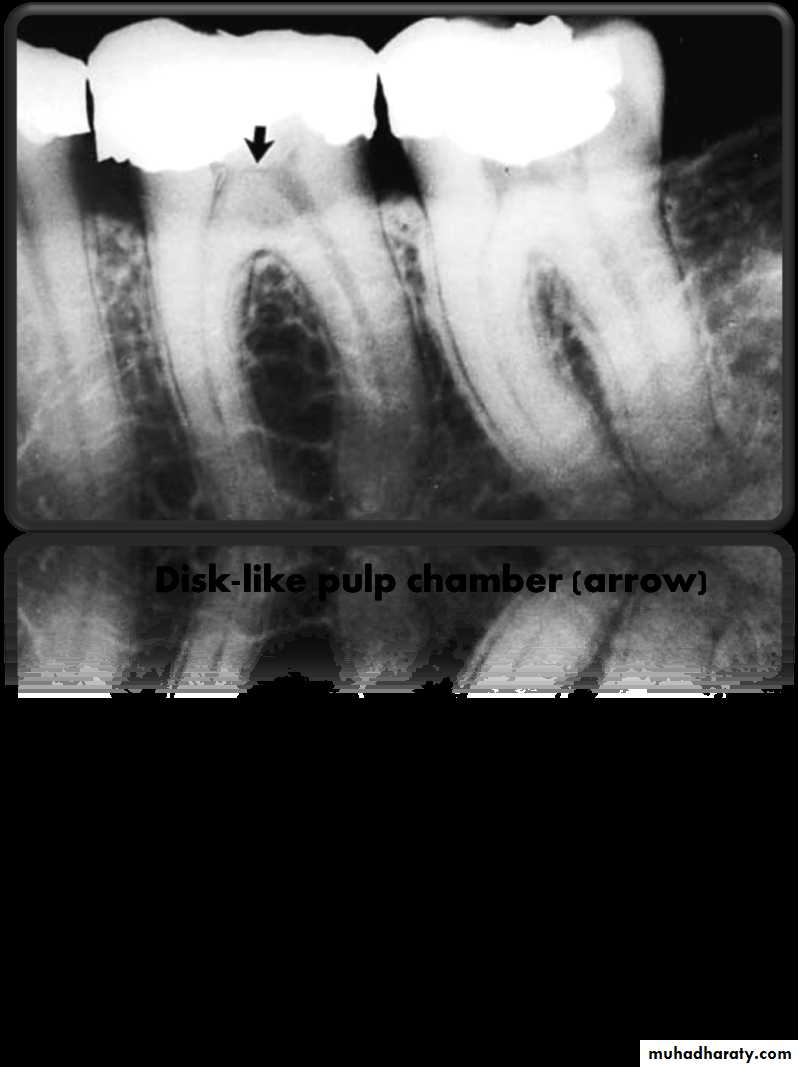

• Access through a small or flattened (disk-like) pulp chamber in a multirooted tooth.

• Proper reading of the preoperative (diagnostic) radiograph to get information about the size and extent of the pulp chamber and internal changes (calcification or resorption).